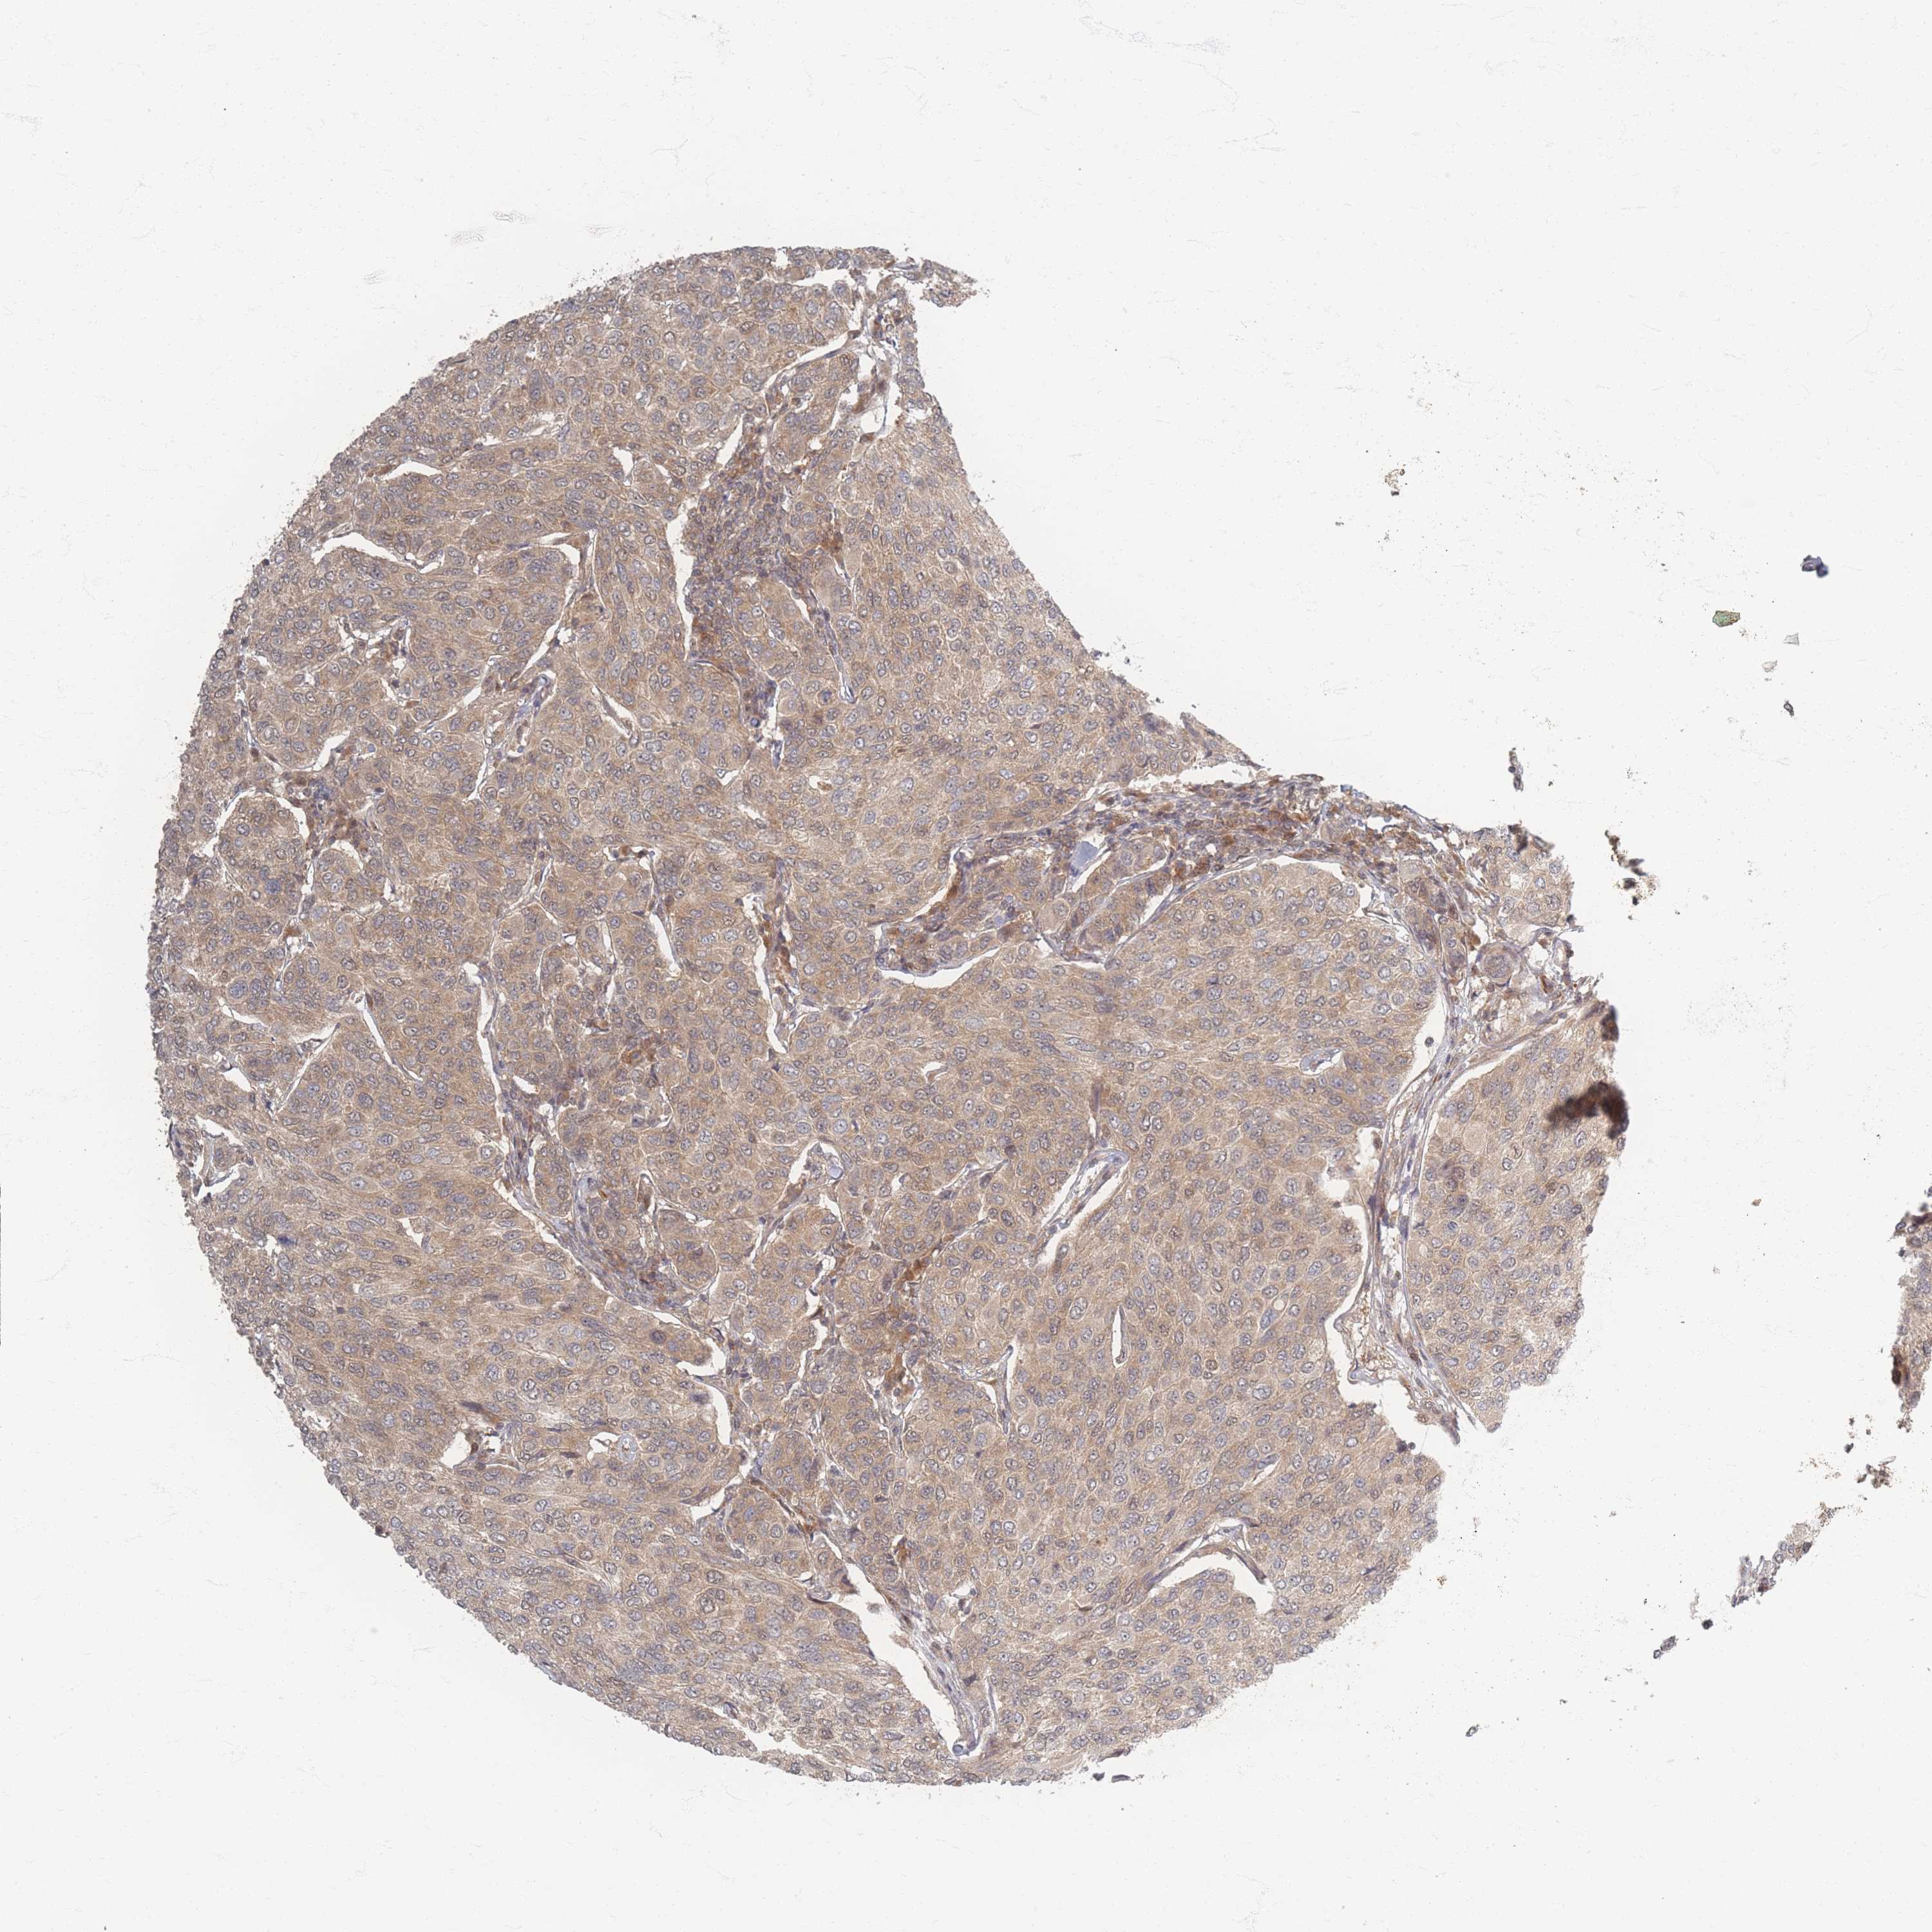

CANCER BREAST CANCER Show tissue menu

BRCA TCGA BRCA VALIDATION PROTEIN EXPRESSION